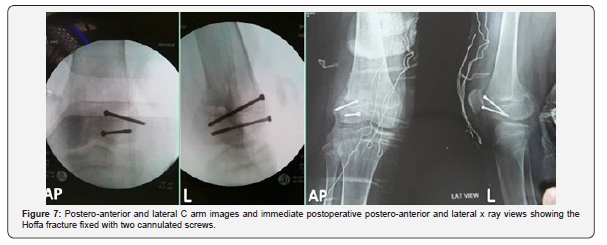

Under spinal anaesthesia, the patient was positioned supine, tourniquet was elevated, and the usual draping was done. Before starting our definitive open reduction and internal fixation diagnostic arthroscopy was done to evaluate the cruciate ligaments, both menisci, and other intra-articular structures and we found no abnormalities except for the coronal fracture of the lateral femoral condyle. Moreover, antero-posterior stability was tested during arthroscopy and our suspicion about this issue was confirmed. Then, lateral parapatellar approach was used, delicate dissection was done until the fracture site was identified. The fractured segment was about 2/3 of the lateral femoral condyle which was displaced posteriorly and laterally with marked posterolateral fibrous adhesions. Moreover, a clear picture of pseudoarthrosis was founded at the fracture site (Figures 4-6).

Conservative management of these fractures supposed to be unsatisfactory as reduction of the fracture fragment is difficult to achieve and to maintain by closed means and it could leads to multiple complications like avascular necrosis, non-union and malunion [2,3,8]. Therefore, surgical stabilization is necessary to achieve satisfactory function [3]. Different approaches have been proposed according to the location of the fracture , including parapatellar approach as reported by Holmes et al.[3] in a case series of five Hoffa fractures and the results were satisfactory. Anterior midline approach was used by Patel et al. [11] in a series of seven adult patients with Hoffa fractures and the results were also good. lateral femoral epicondylar osteotomy was used by Juan M C et al. [12] in a case report of lateral Hoffa fracture and they supposed that this approach could allow to gain extensile exposure to the posterolateral articular structures of the knee, and makes easy the direct reduction and fixation of lateral coronal distal femoral fractures. In this case we did our open reduction, internal fixation with lag screws through a formal lateral parapatellar approach and the result was satisfactory. However, in our case due to fibrous union and the posterio-lateral adhesions, in addition to the obvious pseudoarthrosis, reduction was not so easy. Two reduction forceps were necessary to obtain reduction in both coronal and axial planes after complete excision of the fibrous tissue and pseudoarthrosis from the fracture site.